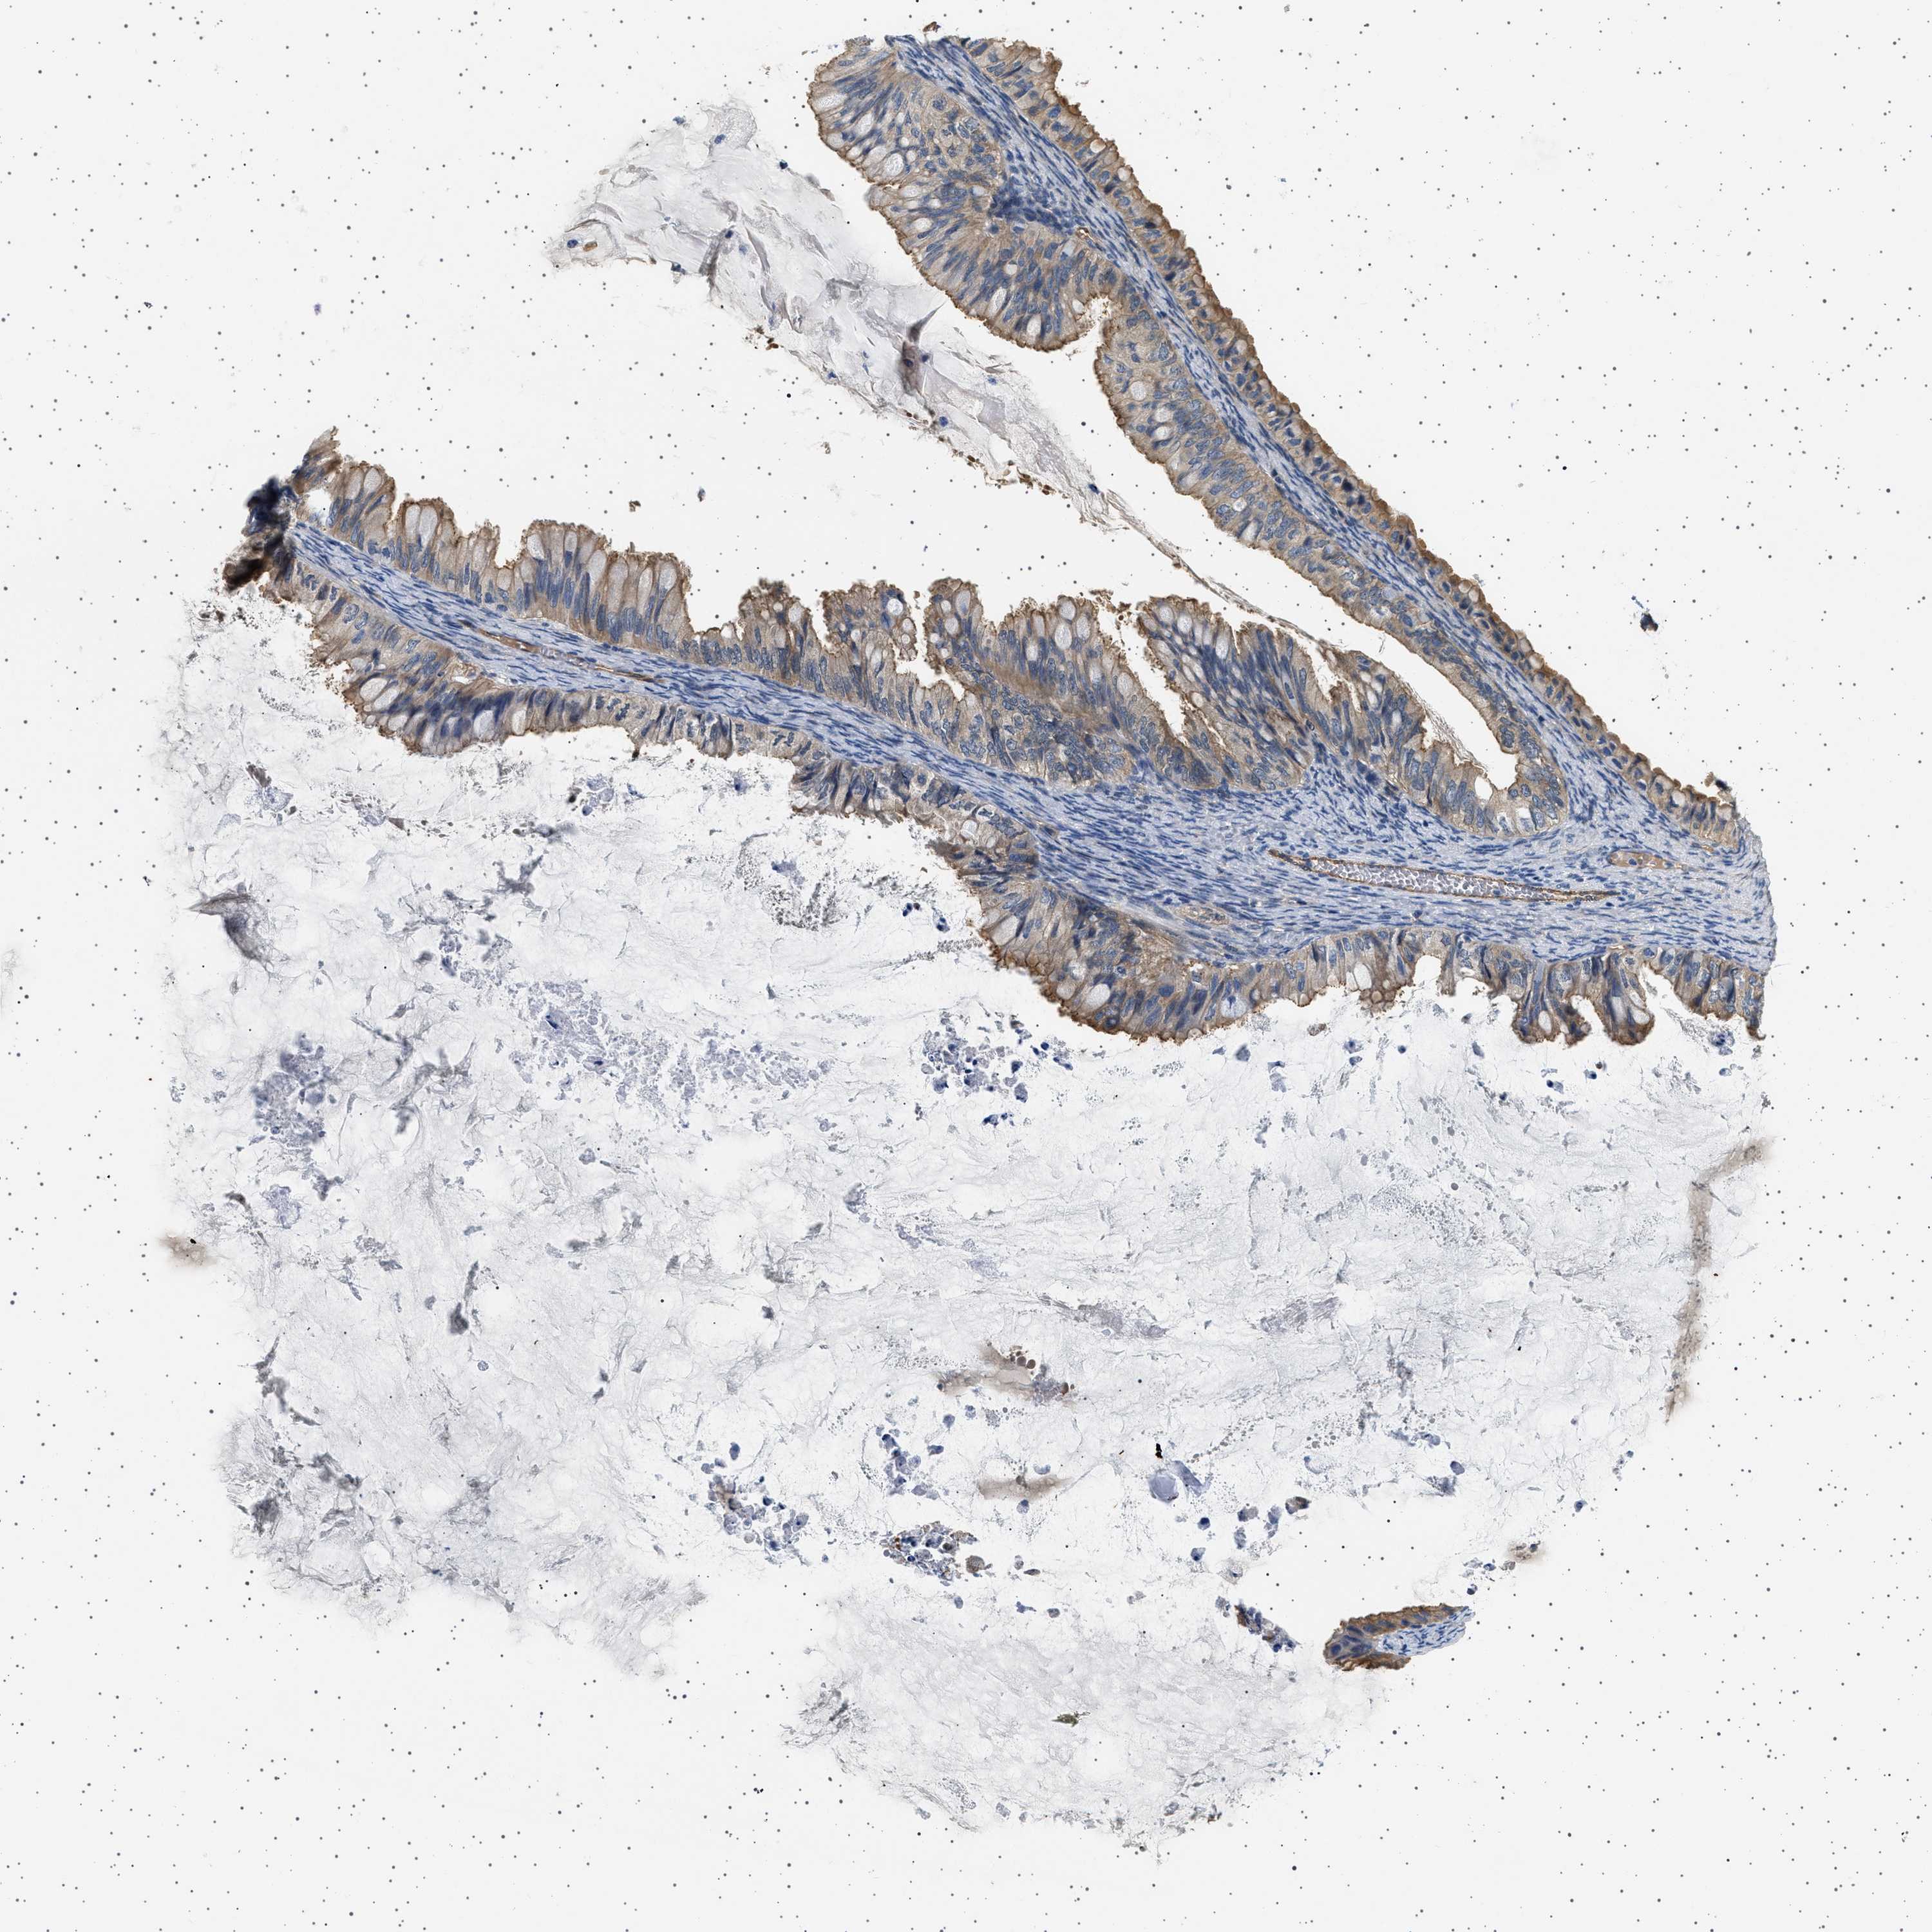

OVARIAN CANCER - Protein expressioni

A mouse-over function shows sample information and annotation data. Click on an image to view it in a full screen mode. Samples can be filtered based on level of antibody staining by selecting one or several of the following categories: high, medium, low and not detected. The assay and annotation is described here.

Note that samples used for immunohistochemistry by the Human Protein Atlas do not correspond to samples in the TCGA dataset.

Antibody stainingi

Antibody staining in the annotated cell types in the current human tissue is reported as not detected, low, medium, or high, based on conventional immunohistochemistry profiling in selected tissues. This score is based on the combination of the staining intensity and fraction of stained cells.

Each image is clickable and will lead to virtual microscopy that enables deeper exploration of all samples and also displays staining intensity scores, fraction scores and subcellular localization as well as patient and tissue information for each sample.

Antibody HPA018096

Cystadenocarcinoma, serous, NOS

Carcinoma, endometroid

Cystadenocarcinoma, mucinous, NOS

Carcinoma, NOS